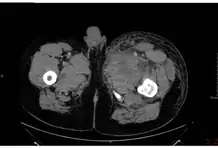

Inhalational anthrax, mediastinal widening

Possible edema and necrosis in a case of injection anthrax.